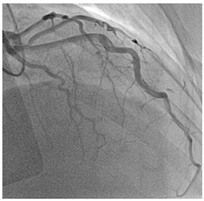

| Type 1 | Classic double lumen appearance with an intimal flap, easily identifiable on imaging. | ![]() Type 1 SCAD of LAD mid-distal vessel. |